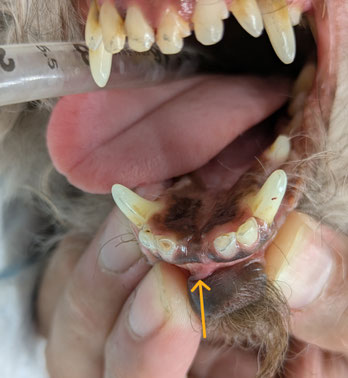

写真は、歯が折れたあとに残った歯根が歯ぐきの中に埋まってしまった状態を示しています。

このような「埋没歯(まいぼつし)」は、外から見ただけではわかりにくく、

📸 レントゲンでの確認

レントゲン写真では、

歯ぐきの中に折れた歯の根が残っている様子が確認できます。

このように、見た目では問題がなくても、

内部で炎症が進行している場合があるため、歯科レントゲン検査が非常に重要です。